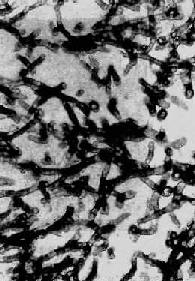

曲菌可在身体许多部位引起病变,如皮肤、耳、鼻腔、眼眶、心、脑、肾、呼吸道、消化道等,而以肺部病变为最常见。曲菌在组织内可引起化脓,形成小脓肿。有时不化脓而发生组织坏死及出血,周围有多数中性粒细胞和单核细胞浸润。在小脓肿和坏死灶内有大量菌丝。曲菌并常侵入血管引起血栓形成,造成血管阻塞,可使组织缺血、坏死。慢性病灶有纤维组织增生,其中有大量淋巴细胞和单核细胞浸润,并杂有多数巨噬细胞和异物巨细胞。病灶内有大量菌丝。曲菌菌丝粗细均匀,直径约2~7μm,有隔,分支状,常成约45°的锐角分支(图18-33),HE染色呈蓝紫色,PAS染色更为清晰,也可用镀银法显示。在陈旧的纤维肉芽肿性病灶内,曲菌菌丝可变形,粗细不匀,部分可膨大呈球状或小囊状。

图18-33 曲菌病

曲菌菌丝粗细均匀,有隔,呈锐角分枝